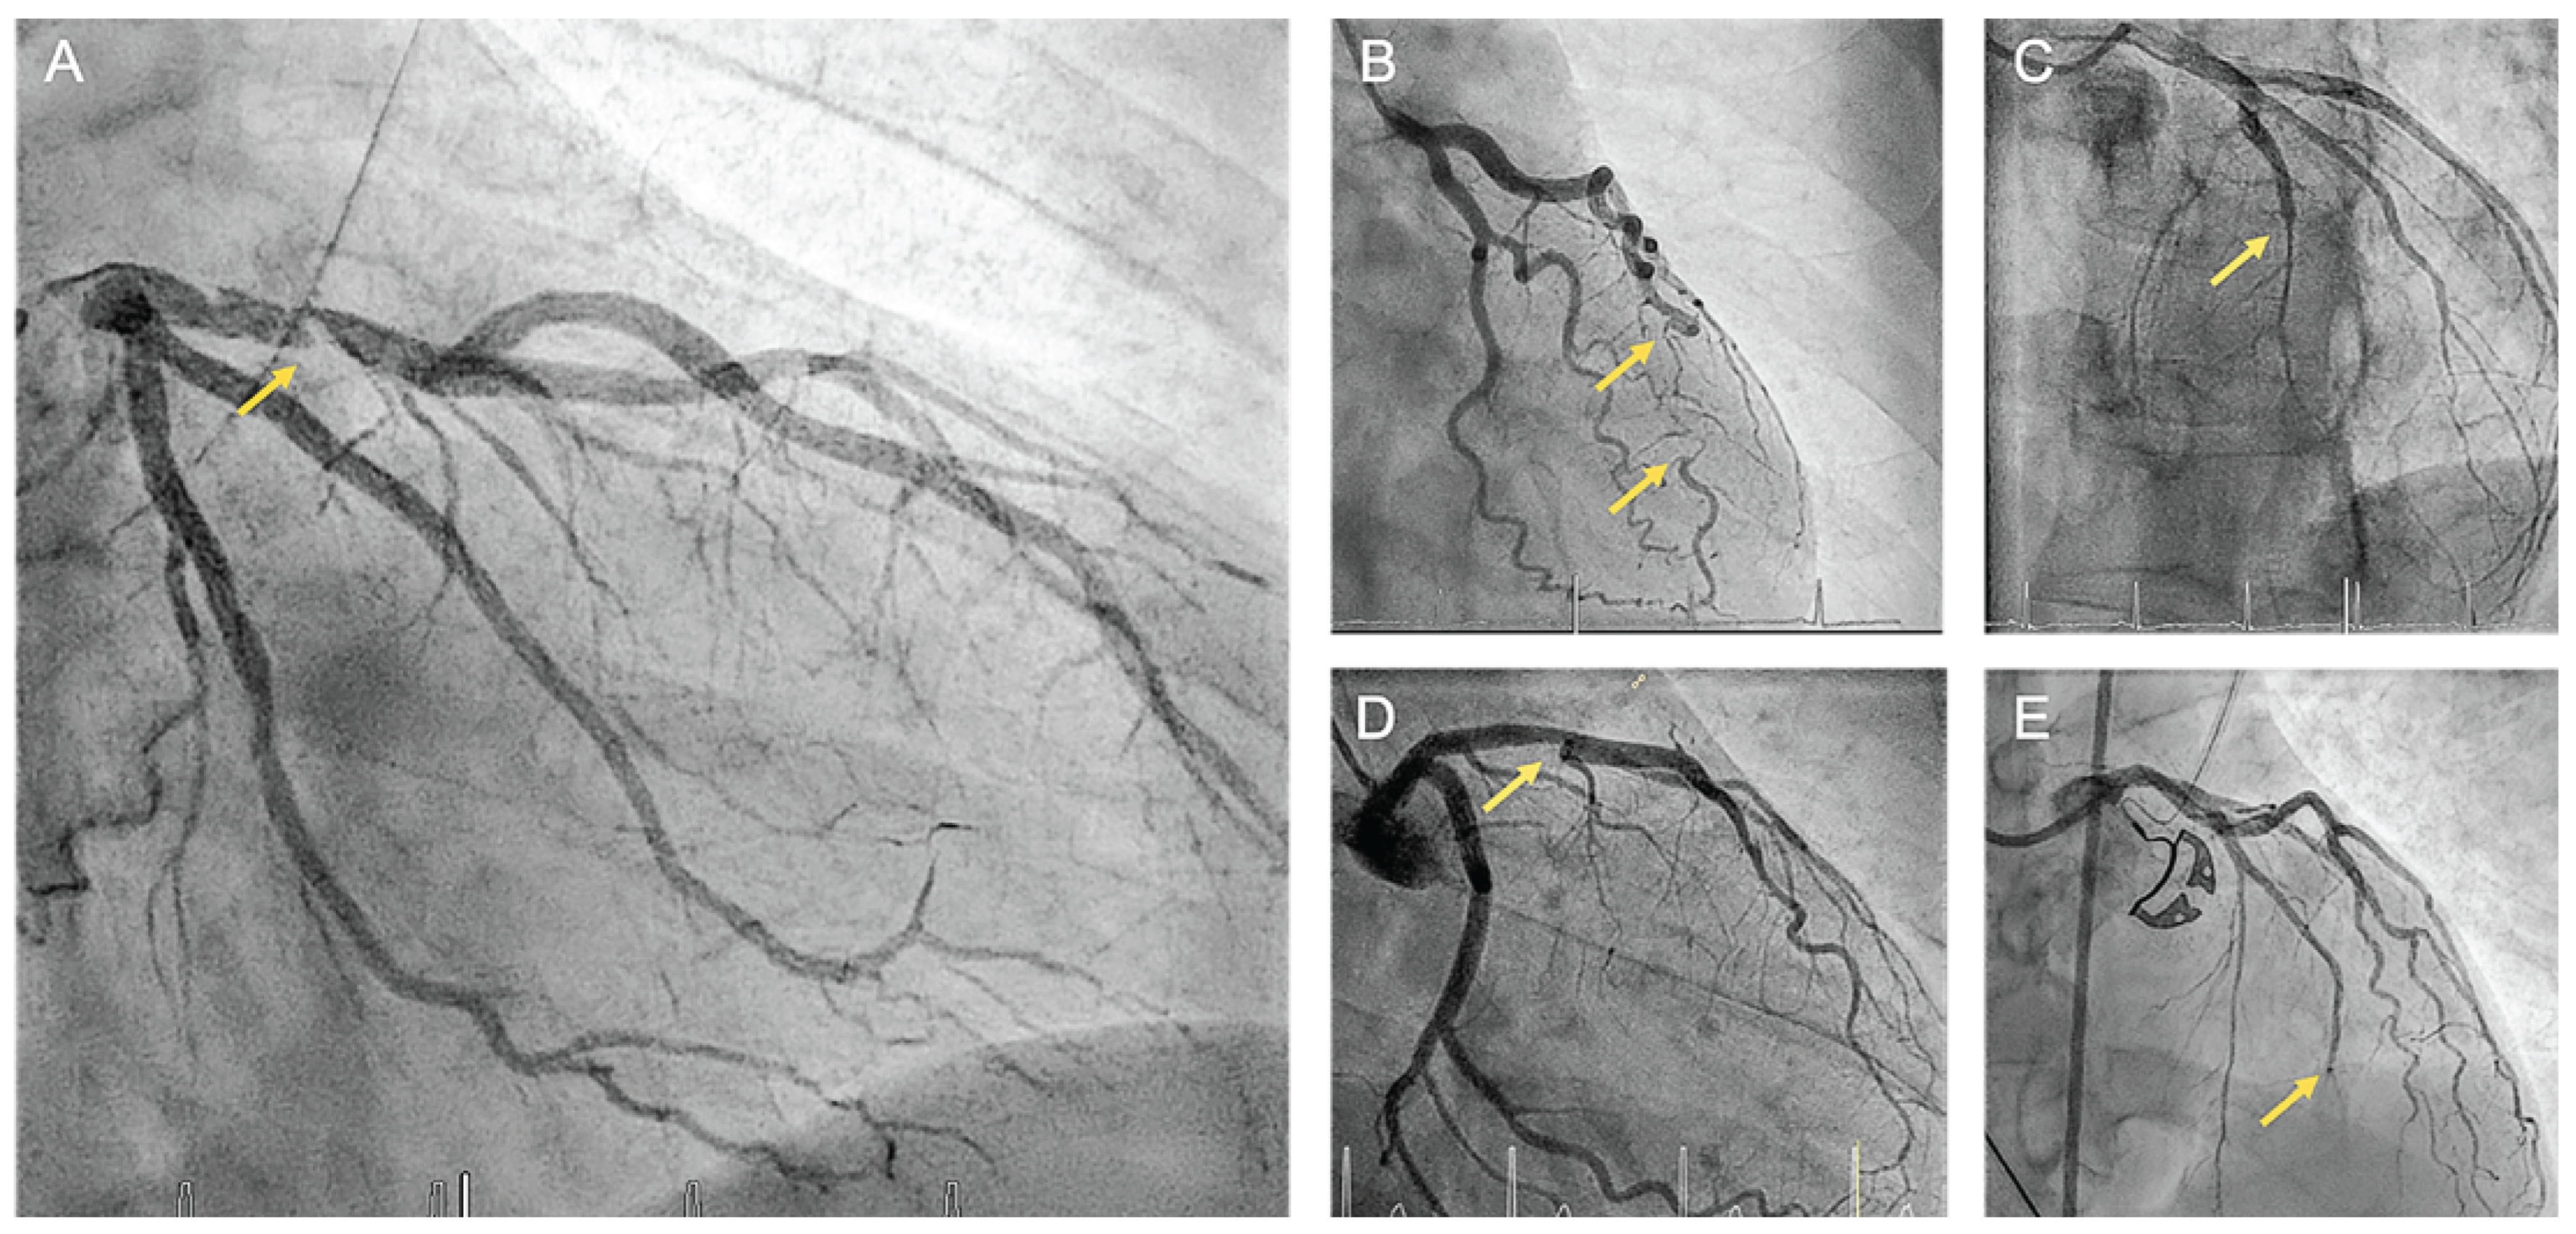

Cardiac Catheterization

Early and accurate diagnosis of SCAD is imperative as the management differs significantly from atherosclerotic myocardial infarction. For patients presenting with ACS or suspected SCAD, the first-line investigation is typically coronary angiography, which allows the categorization of SCAD into distinct angiographic types (Figure 3). SCAD type 1 is characterized by contrast dye staining of the arterial wall and multiple radiolucent lumens. SCAD type 2 refers to a diffuse stenosis resulting from an abrupt change in arterial caliber with variable length and severity, typically exceeding 20 mm. This can be bordered by normal artery segments proximal and distal to the intramural hematoma (type 2a) or extend to the distal tip of the artery (type 2b). SCAD type 3 presents with focal or tubular stenosis typically <20 mm in length mimicking atherosclerosis. Among the different angiographic types, SCAD type 2 is the most frequent (approximately 68%), followed by type 1 (approximately 29%) and type 3 (approximately 3%) [19,57,58]. More recently, a new variant of SCAD referred to as type 4 has been proposed, which is characterized by total occlusion usually affecting a distal vessel. Diagnosis of this rare form is challenging and requires reestablishment of blood flow through coronary intervention. Furthermore, it is necessary to exclude sources of coronary embolism [59].

Figure 3. Angiographic classification of spontaneous coronary artery dissection. (A) type 1; (B) type 2a (in-between arrows); (C) type 2b; (D) type 3; (E) type 4.